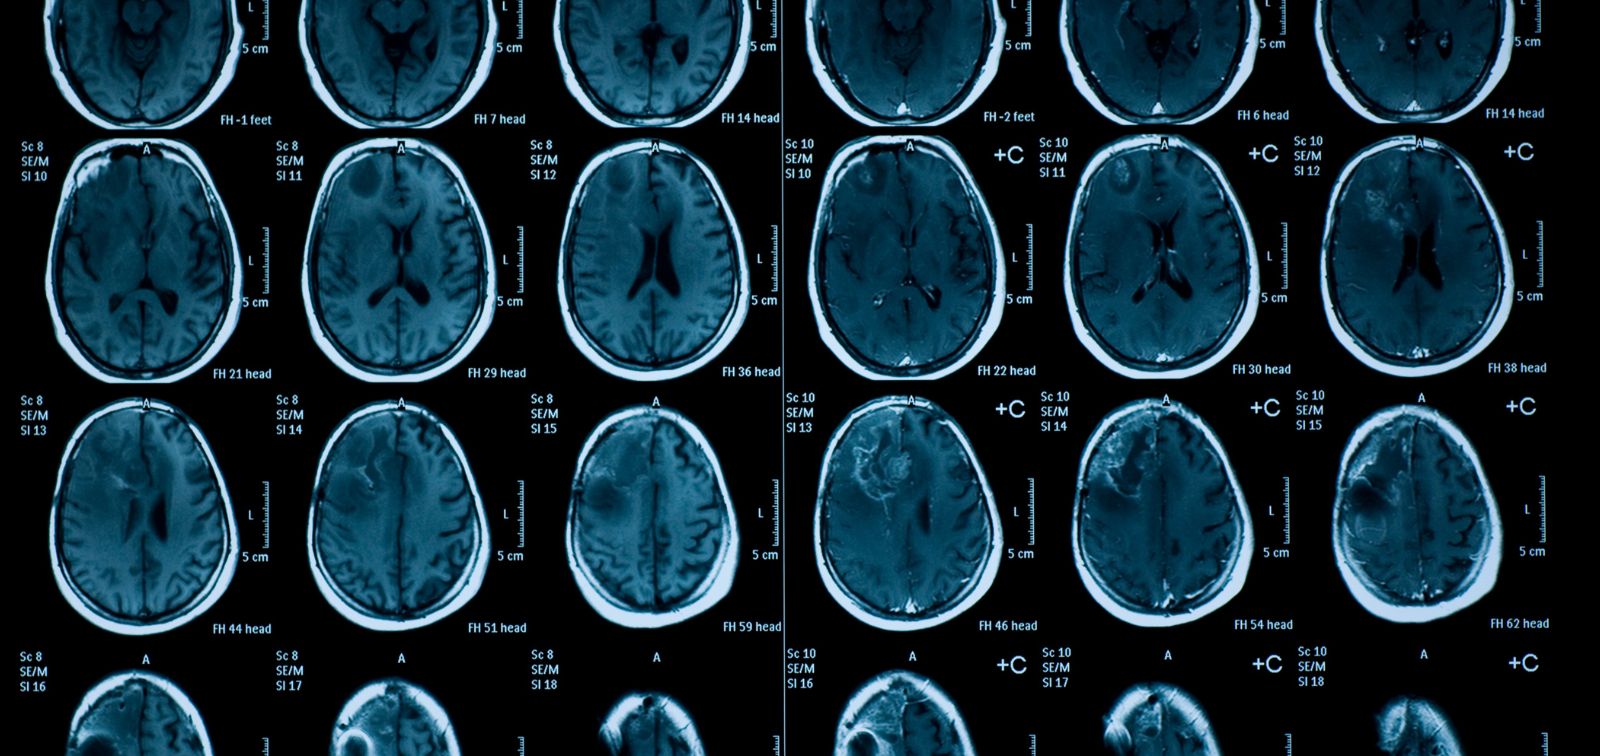

**Research by ISGlobal, supported by the 'la Caixa' Foundation, and partners found that exposure to high ambient temperatures correlates with reduced connectivity in three important brain networks in preadolescents.** Conducted on 2,229 children from the 'Generation R' cohort in the Netherlands, the study analyzed functional connectivity via resting-state MRI, correlating brain activity with temperature data derived from the UrbClim model. **Key findings show reduced connectivity in the medial parietal, salience, and hippocampal networks,** which are crucial for introspection, attention, memory, and learning. Notably, **decreased connectivity was most evident the day before MRI scans and lessened over time.** The study speculates dehydration may explain these effects, emphasizing children's vulnerability to heat. Another significant area of concern is mental health; decreased connectivity in the salience network is associated with anxiety and suicidal ideation. **The findings signal a need for public health policies focused on protecting children from high temperatures, considering their potential impact on cognitive and mental health.**